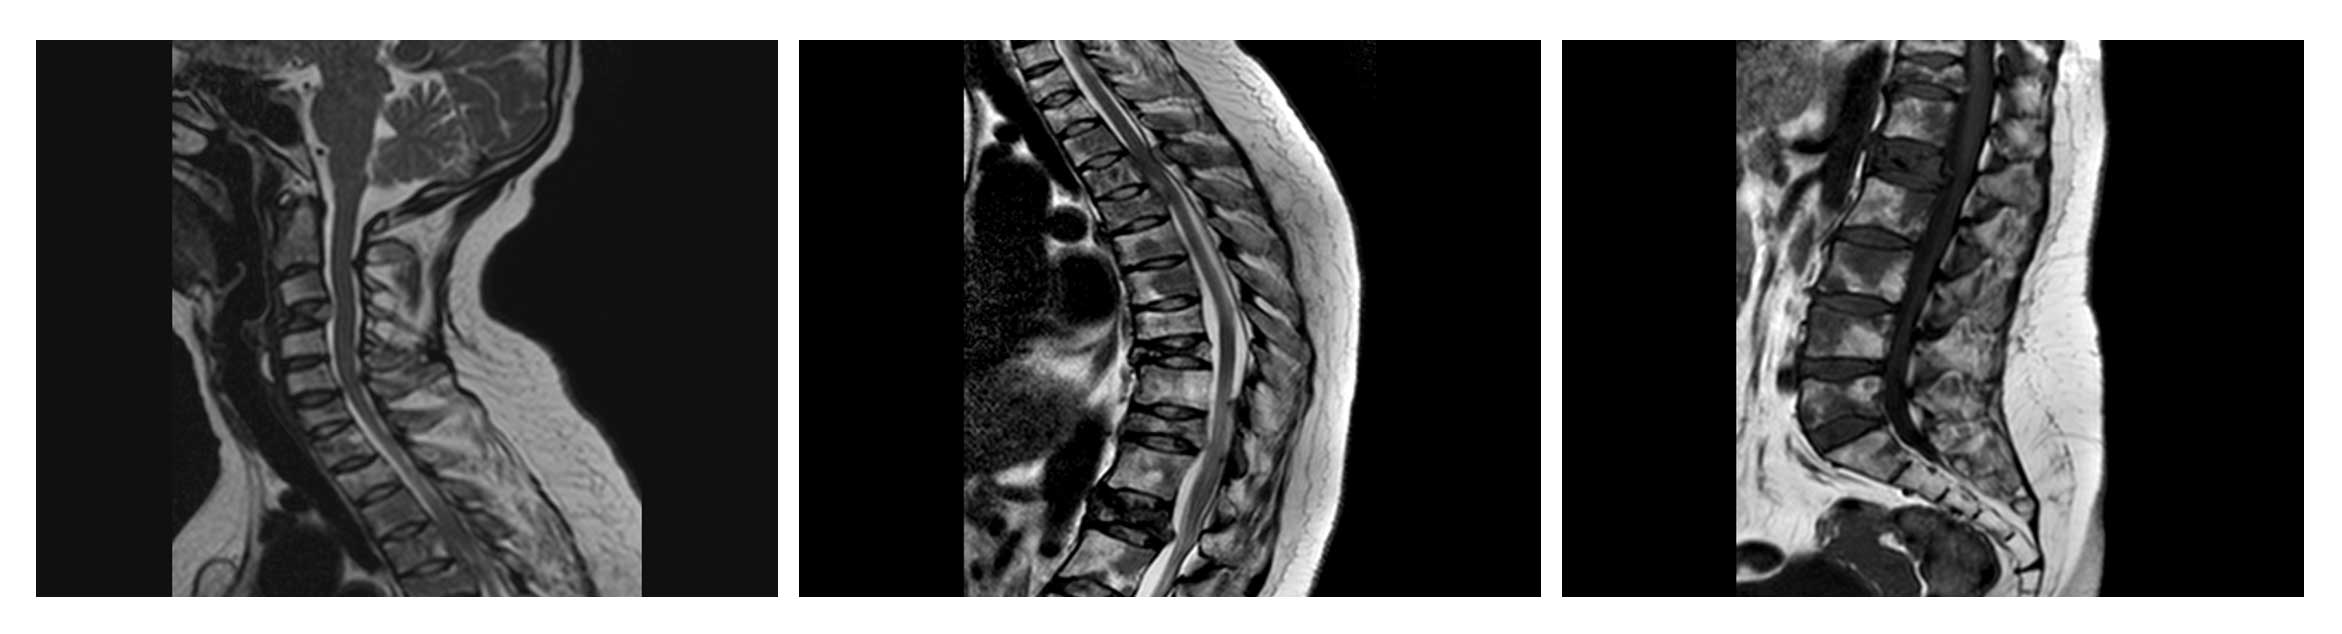

Ameliyat Öncesi: MR’da çökme kırıkları ve kırık riskine eşlik eden üst sırt bölgede omurilik basısı görülmekte.